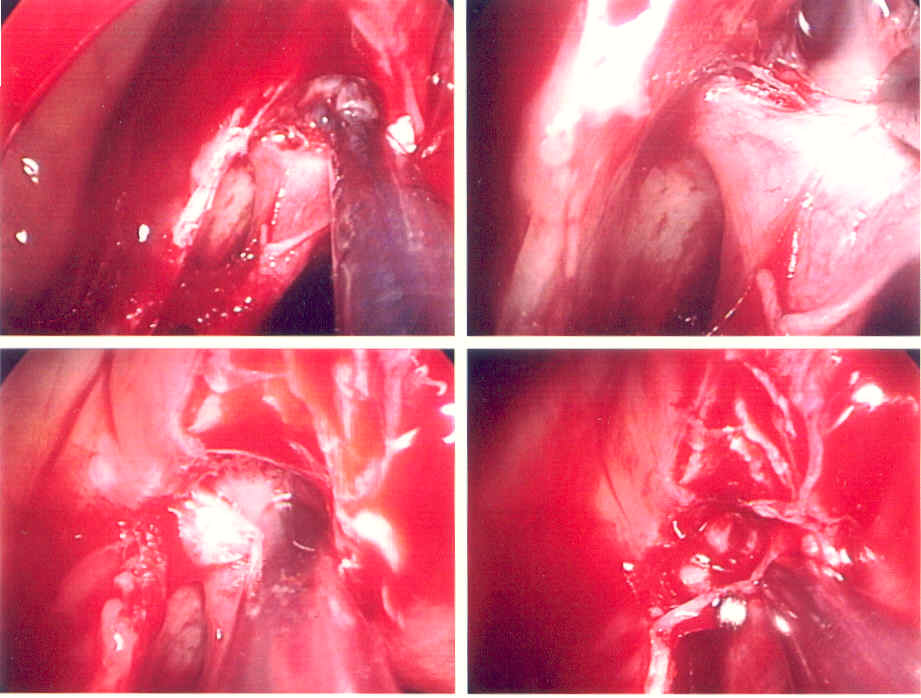

| The picture above depicts a sphenopalatine artery ligation. This procedure is done endoscopically through the nostril. The patient awakes without packing. Recovery is fairly swift, and the results, in properly selected patients, are excellent. | ||||||||||||||||||||

| If conservative measures do not work, then further investigation is warranted. The patient may have a bleeding disorder, sinus disease, a tumor, etc. Packing may be required to temporarily control the bleeding. Surgery may be indicated to straighten a deviated septum or to cauterize vessels. An office evaluation can reveal septal deviation, or prominent septal vessels. When cauterizing the septum only one side at a time can be done, as we risk forming a perforation if both sides are treated at the same time. Sometimes the labial contribution to the septum (Little's area) can be cauterized by retrograde dissection into the columella - this is typicall done if the vessels are low in Little's area. In extreme cases, a sphenopalatine artery ligation may be necessary to get posterior epistaxis under control. Radiological intervention to perform internal maxillary artery embolization can also be performed. |